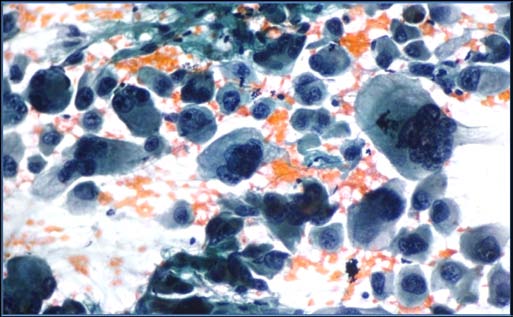

Category III: It is reserved for specimens that contain cells (follicular, lymphoid, or other) with architectural and/or nuclear atypia that is not sufficient to be classified as suspicious for a follicular neoplasm, suspicious for malignancy, or malignant. Management in such lesions is repeat FNAC after an appropriate interval. To be noted that this category is of last resort & should not be used indiscriminately. [8] Category IV: The goal of this category is to identify all potential follicular carcinomas and refer them for a diagnostic lobectomy. Although these cytomorphologic features do not permit distinction from a follicular adenoma (FA), they are reportable as Follicular Neoplasm (FN) or suspicious of Follicular Neoplasm (SFN), leading to a definitive diagnostic procedure, usually lobectomy. [11,12,13] The term SFN is preferred by some laboratories over FN for this category because a significant proportion of cases (up to 35%) prove not to be neoplasms but rather hyperplastic proliferations of follicular cells, most commonly those of multinodulargoiter. [14][15][16][17] About 15% to 30% of cases called FN/SFN prove to be malignant. [11,14,16] The majority of FN/SFN cases turn out to be FAs or adenomatoid nodules of multinodulargoiter, both of which are more common and outnumbers the Follicular carcinoma. Category V: FNAC can diagnose many of the thyroid cancers with fair accuracy, especially papillary thyroid carcinoma (PTC) which can be diagnosed with certainty by FNA. But the nuclear and architectural changes of some PTCs are subtle and focal. This is particularly true of the follicular variant of PTC, which can be difficult to distinguish from a benign follicular nodule. [18] Other PTCs may be incompletely sampled and yield only a small number of abnormal cells. [19] If only 1 or 2 characteristic features of PTC are present or if they are only focal and not widespread throughout the follicular cell population, or if the sample is sparsely cellular, a malignant diagnosis cannot be made with certainty. Such cases occur with some regularity, and they are best classified as suspicious for malignancy," qualified as "suspicious for papillary carcinoma." Such cases suspicious for papillary carcinoma are resected by lobectomy or thyroidectomy. Most (60%-75%) prove to be papillary carcinomas, and the rest are usually FAs. [11,14,16] The same general principle applies to other thyroid malignancies like medullary carcinoma and lymphoma, but these are less frequent than PTC. Such cases were considered after correlating the other findings like serum calcitonin and calcium levels and other relevant data in medullary carcinoma.

The malignant category is used whenever the cytomorphologic features are indicative of malignancy. After confirming the malignancy the sub classification was done after summarizing all the results. Approximately 3% to 7% of thyroid FNAs have conclusive features of malignancy, and most are papillary carcinomas. [11,14] Malignant lesions are usually treated bythyroidectomy, with some exceptions (e.g., metastatic tumors, non-Hodgkin lymphomas, and undifferentiated carcinomas). According to studies the positive predictive value of a malignant FNA interpretation is 97% to 99%.

We here practiced mainly the non-aspiration technique in almost all cases for studying cytology and found that it is better than aspiration technique. Aspiration technique is associated with low cellularity and more blood as compared to non-aspiration method. We recommend the non-aspiration method for FNAC of thyroid lesions. Similar suggestions by different studies like Maurya et.al [20] also recommend the non-aspiration technique better for thyroid lesion evaluation by FNAC. The study found thatit is difficult to differentiate follicular/Hurthle cell adenoma from carcinoma on cytological assessment because cytology cannot evaluate the criteria of vascular or capsular invasion or of intrathyroid spread. But the papillary carcinoma, Anaplastic carcinoma and medullary carcinoma can be diagnosed by characteristic cytological features.